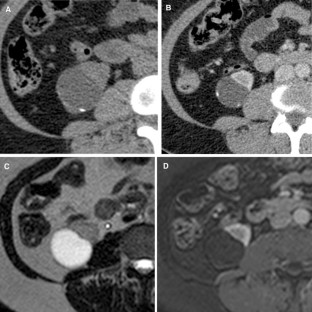

Fig. 2